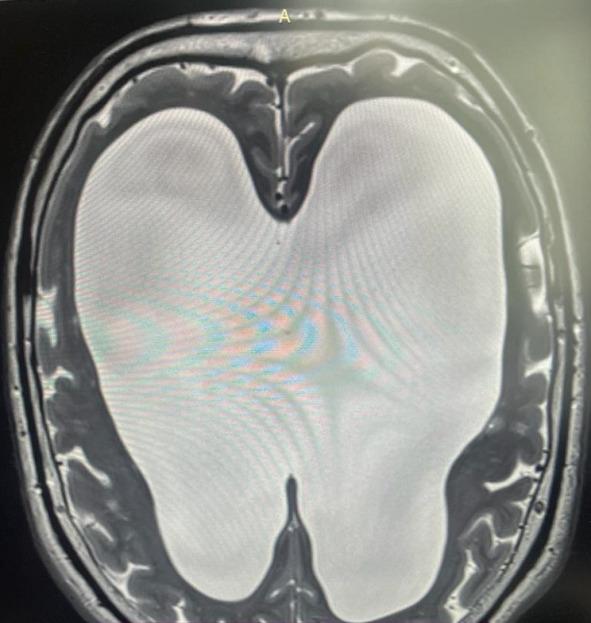

Помимо всего этого, у мозга есть еще одна потрясающая способность — способность сжиматься без какой-либо травмы вещества мозга, если в голове постепенно уменьшается полезный объем. На фото вы видите МРТ человека с нормотензивной гидроцефалией (стр.7), а рядом обычное МРТ (стр.6).

При нормотензивной гидроцефалии объем желудочков мозга увеличивается постепенно. Вы видите, насколько мало места в черепе осталось непосредственно для головного мозга, примерно в два раза меньше нормального объема. И вот этот человек с такими проблемами в голове ходил на работу, начал отмечать замедленность мышления, снижения скорости обработки информации, поэтому обратился к неврологу. Нейрохирурги выполнили ему операцию, после которой желудочки мозга стали нормального размера. И он вновь стал думать так же быстро и великолепно запоминать информацию. И за несколько месяцев сжатия в его мозге не погибли клетки, там не возникло участков некроза, видимых на МРТ. Представьте, если бы мы сдавили мышцы бедра или предплечья. Уже через несколько часов был бы некроз мышц, а здесь несколько месяцев — и без последствий. Таким образом, компенсаторная способность к уменьшению объема у мозга совершенно поражает воображение.